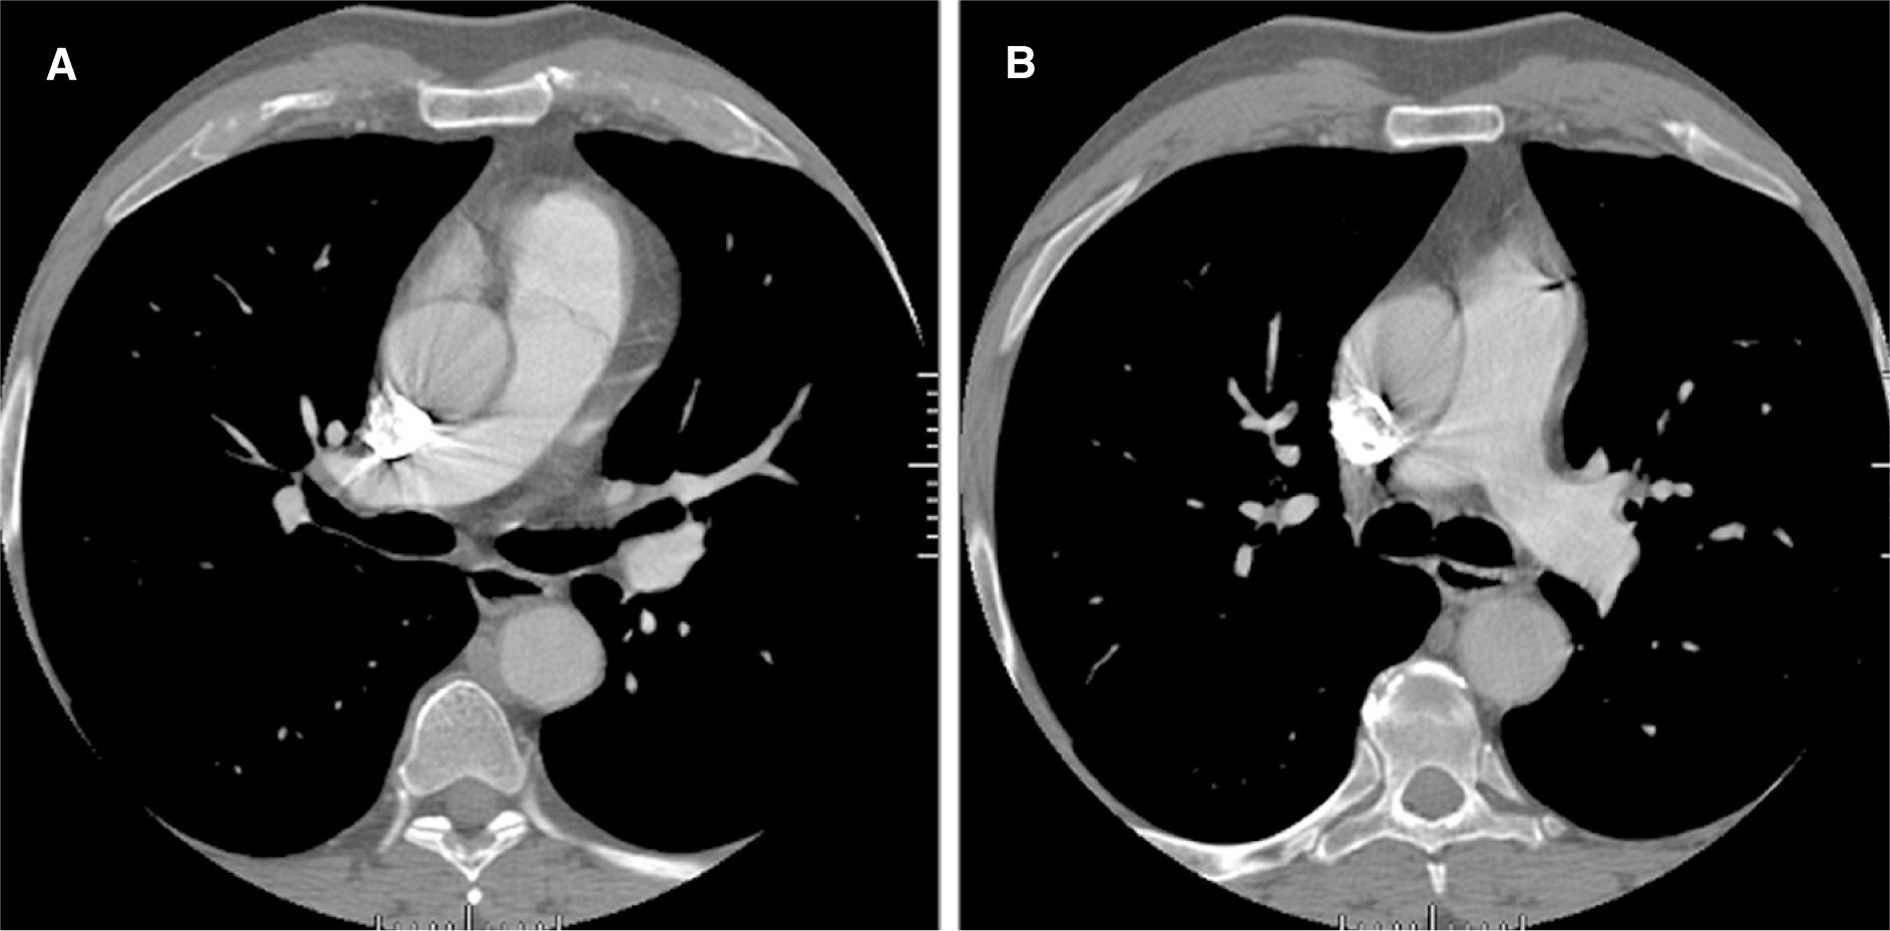

Embolia polmonare (PE) è l’occlusione del sistema venoso dei polmoni causata da un embolo o trombo proveniente da altre parti del corpo, e nel 95% dei casi trombosi venosa proveniente dal mosto piernas.Un embolia o trombosi della circolazione venosa raggiunge la giusta camere del cuore e lo spinge nei polmoni al resto del sangue venoso. Se il trombo è piccolo non succede nulla (e non è raro che questo accade molto spesso), ma se si attivano altri meccanismi di grandi dimensioni. Una parte del polmone smette di ricevere sangue venoso per ossigenarlo, poiché le vene sono occluse. Queste aree collassano e l’aria non può passare a loro. Il cuore invia ancora la stessa quantità di sangue, ma lo fa con meno vene di prima, quindi è costretto a fare più sforzo e spendere più energia. Inoltre, c’è più sangue per meno spazio polmonare, quindi non tutto il sangue che passa può essere ossigenato correttamente. L’area interessata inizia a gonfiarsi. Inizia ad accumulare liquido ostacola l’espansione dei polmoni, mentre i recettori nervosi che stimolano respirazione irritata, causando la persona a respirare PET ad alta frequenza e profondamente.